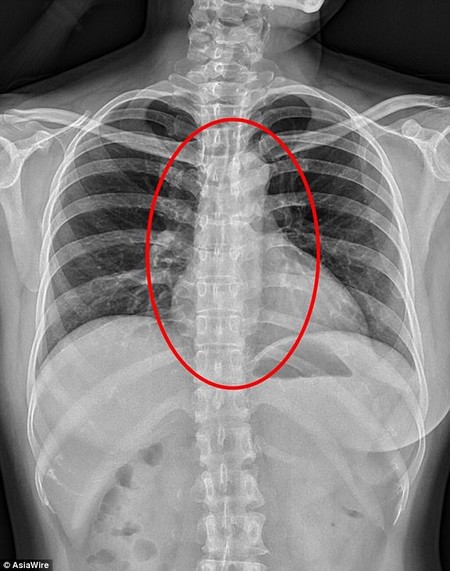

Đặng sau đó lập tức được đưa đến bệnh viện, nơi các bác sĩ chụp phim X-quang và phát hiện thấy một dị vật bên trong cơ thể bệnh nhân, khi lấy ra các bác sĩ mới giật mình, đó là một chiếc... bao cao su.